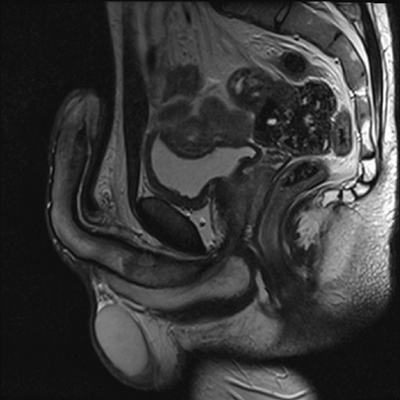

T1w-MRI (Sagittal) post IV contrast with no enhancement of right corpus cavernosum thrombus.

MRI (see figure below), contrast-enhanced ultrasound (CEUS) or ultrasound doppler (USS) can be used to confirm the presence of the thrombus within the corpus cavernosum, as a well-defined non-enhancing mass [5,8-12]. Although CEUS is cheaper than performing serial MRI imaging, it is operator dependent [5].

Segmental thrombosis of the corpus cavernosum has a characteristic appearance on MRI and should be suspected in men presenting with acute perineal pain associated with a palpable penile shaft mass or perineal mass with or without a prolonged erection. The thrombus size appears to reduce after three months of anticoagulant or antiplatelet treatment and erectile function improves gradually within six months without the need for ongoing pharmacotherapies. However, long-term outcomes are unknown and larger case series are required to establish a unified practice in the management of this condition.

MRI of the penis / pelvis will identify thrombus within the corpus cavernosum which unlike malignant lesions appears smooth with no contrast enhancement.